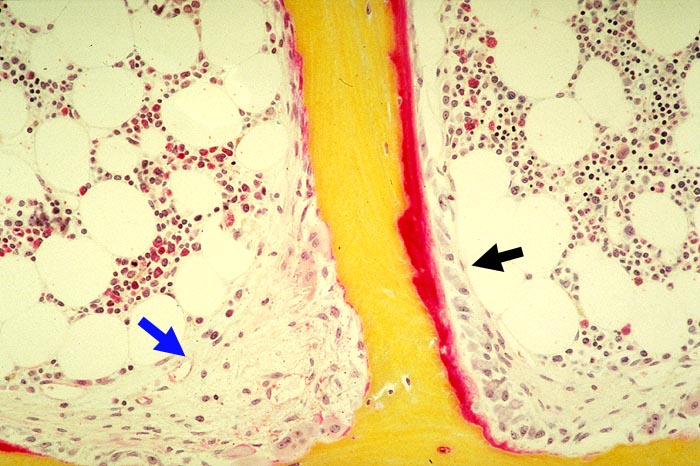

Stark erhöhter Spongiosaumbau: ► Resorptionslakune mit Osteoklasten und endostaler Fibrose (Fibroosteoklasie). ► Osteoblasten- und roter Osteoidsaum (Osteoidose).

Sekundärer Hyperparathyreoidismus bei chronischer Niereninsuffizienz.